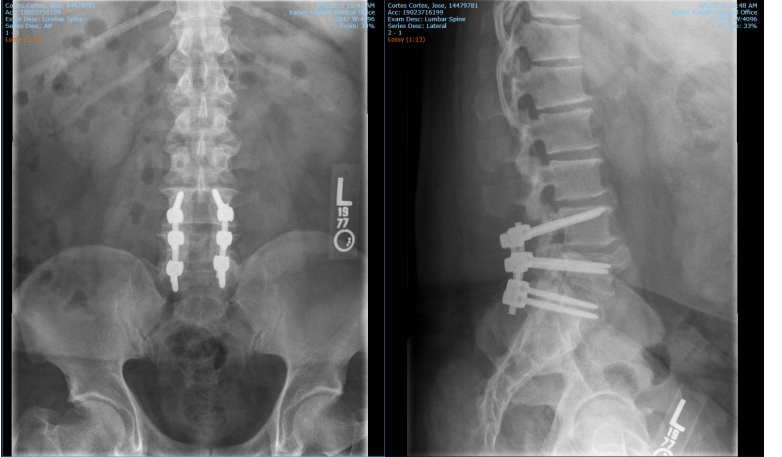

Please help us raise funds to help my husband, José Cortes Cortes, to receivemedical attention. He was detained by ICE without having committed any crime or having any bad record. This has been a very traumatic experience for us. José is currently recovering from back surgery and has not been given any medical attention since his detention. The agents showed no regard for his condition. During the incident, they sped off with him without closing the door or fastening his seatbelt, causing him to be thrown out of the car when they turned the corner. When I tried to intervene, the agents physically hurt me as well, and I had to go to the hospital to get checked out. We are raising funds to cover the medical expenses. We thank you in advance from the bottom of our hearts. May God bless you and multiply your kindness.